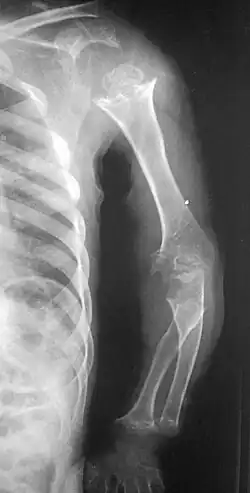

| Pseudoachondroplasia. Shoulder and humerus. Note the dysplastic proximal humeral epiphysis, metaphyseal broadening, irregularity and metaphyseal line of ossification. These changes are collectively known as "rachitic-like changes". Lesions are bilateral and symmetrical. | |

Skeletal radiography

Accurate assessment of plain radiographic findings remains an important contributor to diagnosis of pseudoachondroplasia. It is noteworthy that vertebral radiographic abnormalities tend to resolve over time. Epiphyseal abnormalities tend to run a progressive course. Patients usually suffer early-onset arthritis of hips and knees. Many unique skeletal radiographic abnormalities of patients with pseudoachondroplasia have been reported in the literature.[2][7][4]

- Together with rhizomelic limb shortening, the presence of epiphyseal-metaphyseal changes of the long bones is a distinctive radiologic feature of pseudoachondroplasia.

- Dysplastic/hypoplastic epiphyses especially of shoulders and around the knees.

- Metaphyseal broadening, irregularity and metaphyseal line of ossification. These abnormalities that are typically encountered in proximal humerus and around the knees are collectively known as "rachitic-like changes".

- Radiographic lesions of the appendicular skeleton are typically bilateral and symmetric.